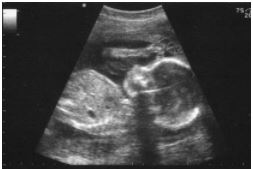

‘This is what kills the baby, right?’: Clinic tried, but failed to hide reality of abortion from mom

(LiveActionNews) – Abortion clinic workers often try to hide the reality of the abortion procedure from the patients they meet. In one particular abortion clinic, the counselors avoided using the word “baby.” Wendy Simonds, a pro-choice feminist who interviewed clinic workers and watched abortions at the clinic, said the following: